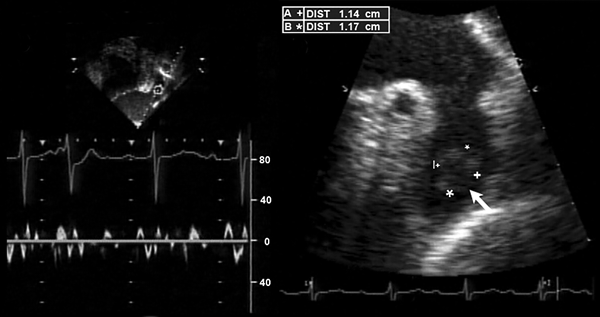

Фиброз с просветами около легочной вены после абляции. Gal P, Marrouche N. Eur Heart J. 2017;38:14–9.

• Эхокардиография трансторакальная.

• Эхокардиография чреспищеводная (по показаниям).

Холтеровское мониторирование в течение суток позволяет отследить работу сердца во время физических нагрузок, отдыха и сна. УЗИ сердца показывает размеры предсердий и структурные патологии (пороки сердца и др.). Также иногда проводят ЭКГ во время физической нагрузки (ходьбы на беговой дорожке или занятий на велотренажере), чтобы оценить работу сердца в такие моменты.